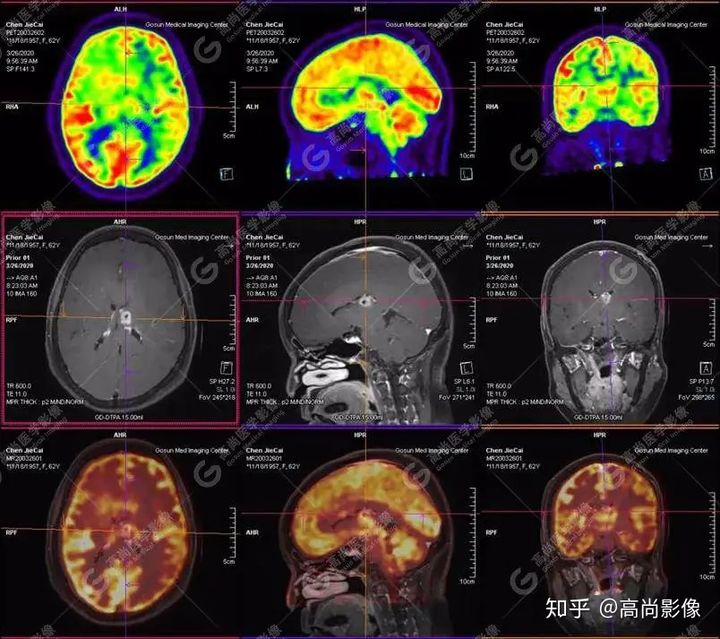

【PET-MR融合診斷】

左側(cè)顳葉、頂葉、左側(cè)基底節(jié)區(qū)及胼胝體部多發(fā)結(jié)節(jié)狀高代謝病灶,部分合并囊變、出血,MR平掃+增強(qiáng)示不均勻輕、中度強(qiáng)化,綜合考慮為顱內(nèi)原發(fā)惡性腫瘤,以淋巴瘤可能性大

淋巴瘤病變多位于中線兩旁的深部腦實(shí)質(zhì)、側(cè)腦室周?chē)澳X表面,甚少累及腦膜和顱骨,幕上多于幕下,呈分葉狀或握拳狀,水腫及占位效應(yīng)較輕,部分病灶內(nèi)可見(jiàn)囊變、出血及其邊緣的硬環(huán)征、尖角征、臍凹征,增強(qiáng)掃描呈現(xiàn)的“臍凹征或者“握拳征”是淋巴瘤較為特征性的一個(gè)表現(xiàn)。

18F-FDG PET PET顯像中呈明顯高代謝病灶。

顱內(nèi)惡性淋巴瘤對(duì)18F-FDG的攝取率很高,一般SUV在5~10以上,18F-FDGPET顯像中攝取明顯高于正常腦皮層,因此具有特征性。